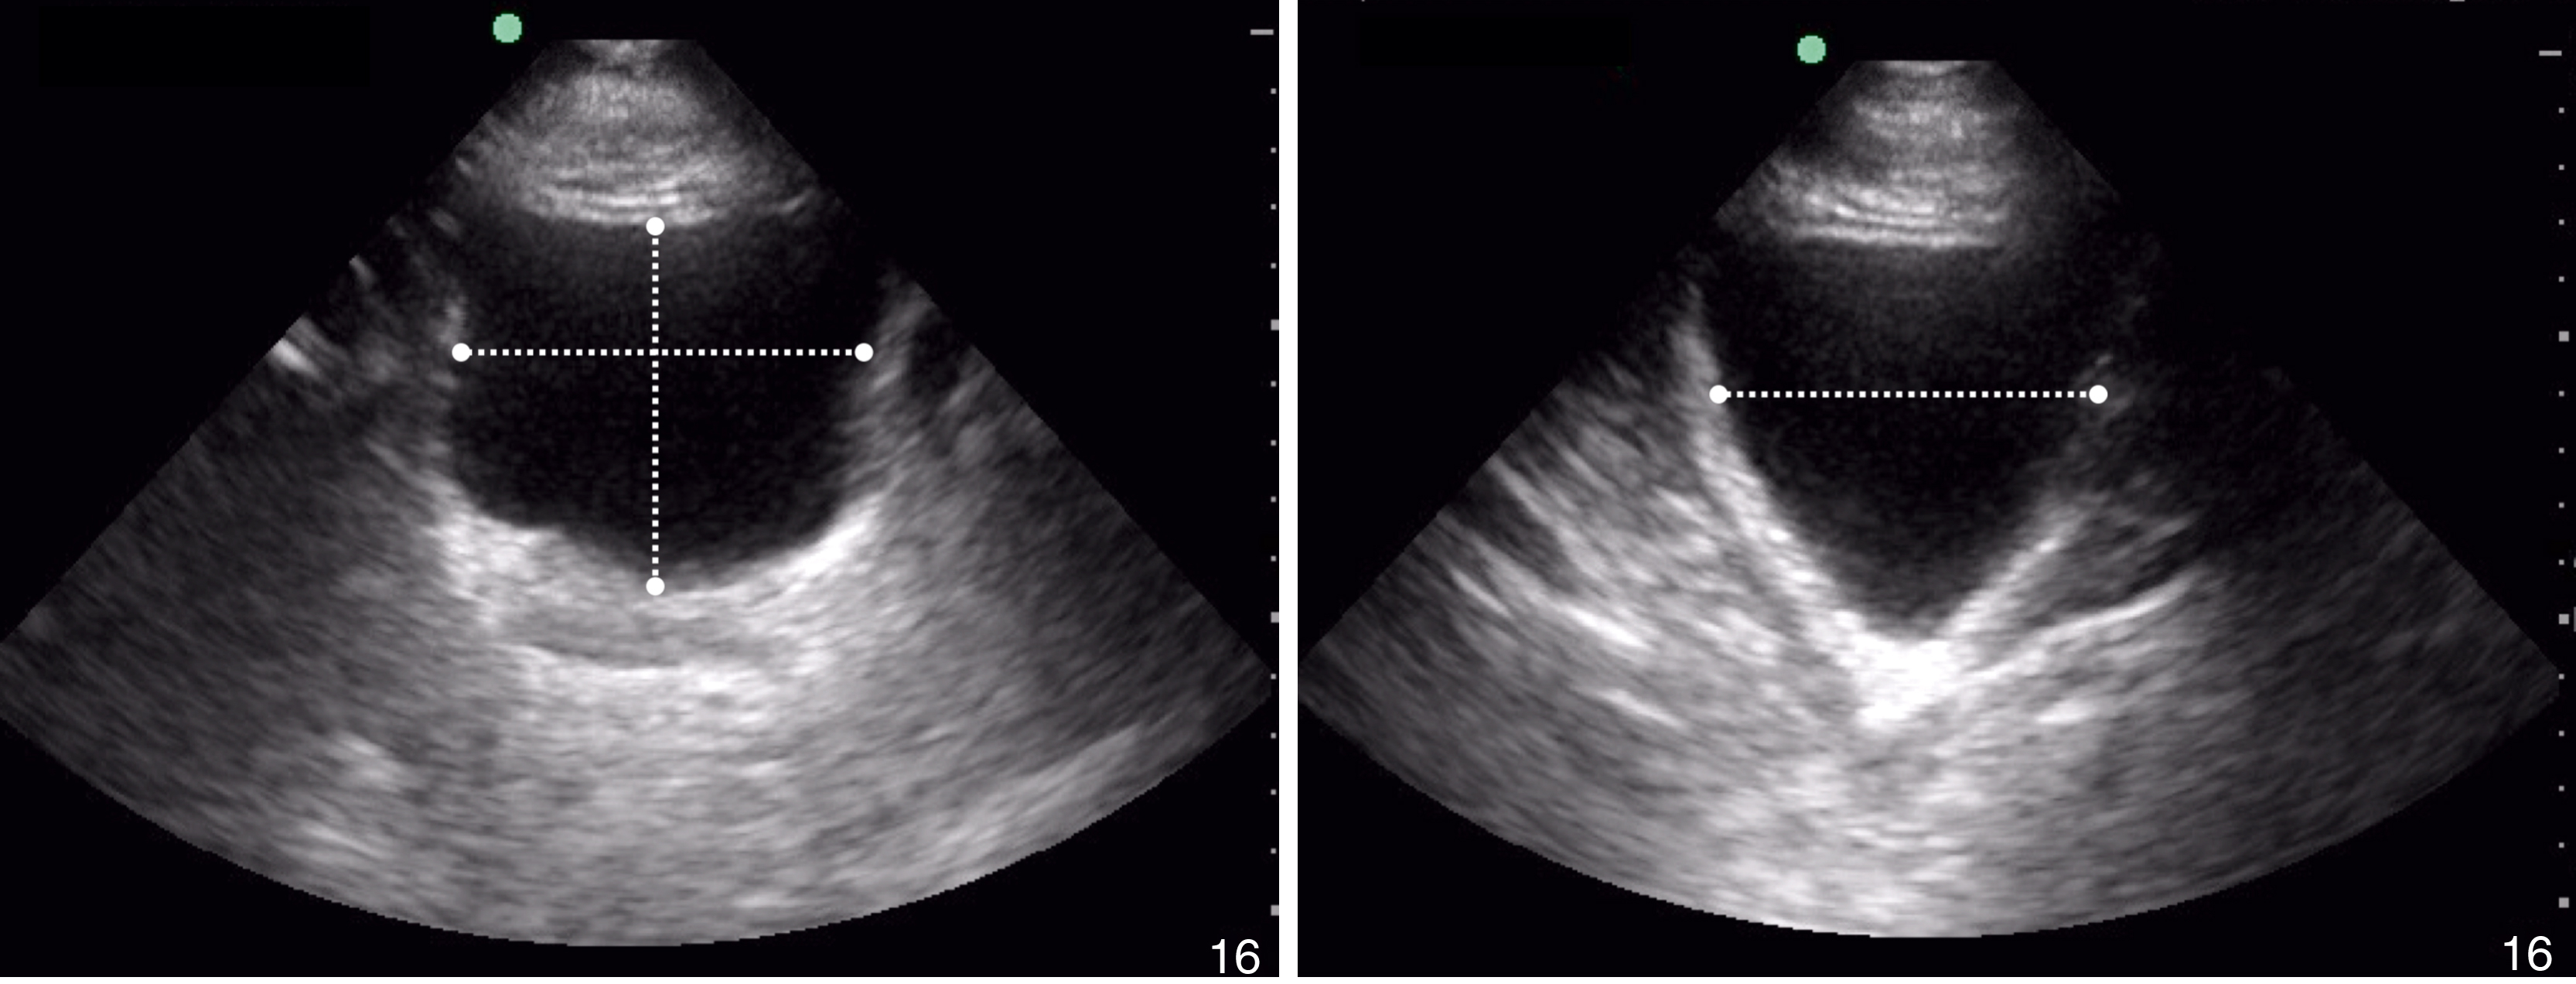

Renal US includes orthogonal views of the kidneys, with an emphasis on visualization of the renal calyces/pelvis. The sonographic windows for the two kidneys are similar to those used in the trauma upper quadrant views. The bladder view is performed from the suprapubic window in transverse and sagittal planes. Ureteral jets can be assessed by placing color Doppler over the trigone of the bladder in the transverse view. Bladder volume calculations ( Fig. e3.5 ) may be performed with on-machine calculators or by using the formula:

Bladder volume measurements.